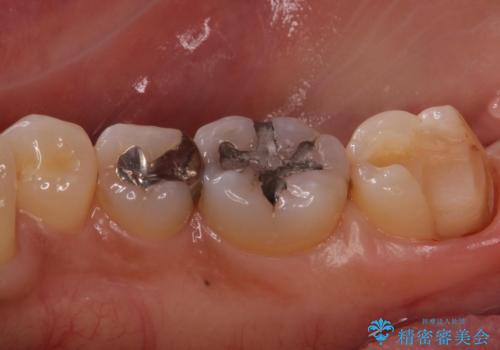

- 右下奥歯が気になるとのことで来院された患者様です。

銀の詰め物の適合が悪く、歯と銀歯の間に歯茎が入り込んできている状態でした。

銀歯を除去し、適合の良いゴールドアンレーで修復していきます。